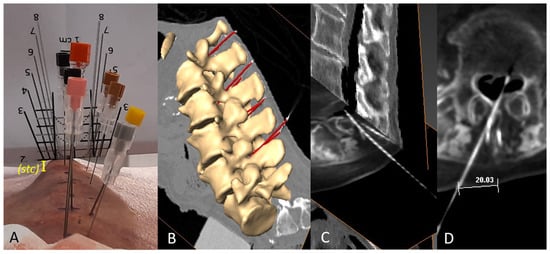

2.4. Needle Insertion

2.5. CT and 3D Reconstruction

2.6. Anatomical Illustration of Needle Path and Affected Structures